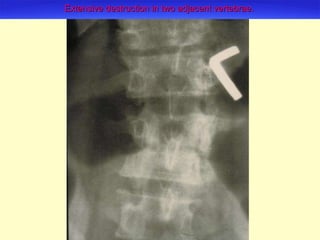

Extensive destruction in two adjacent vertebrae.

Two vertebrae collapsed to the height of one.

The vertebral lesions are usually anterior in location, often triangular in shape.  The bony structure adjacent to both sides of the disk becomes eroded, leading to the seemingly narrowing of inter-vertebral disk space.

As a result of the anterior lesion, the disk or disks collapse, building a triangular shape, leading the typical gibbus